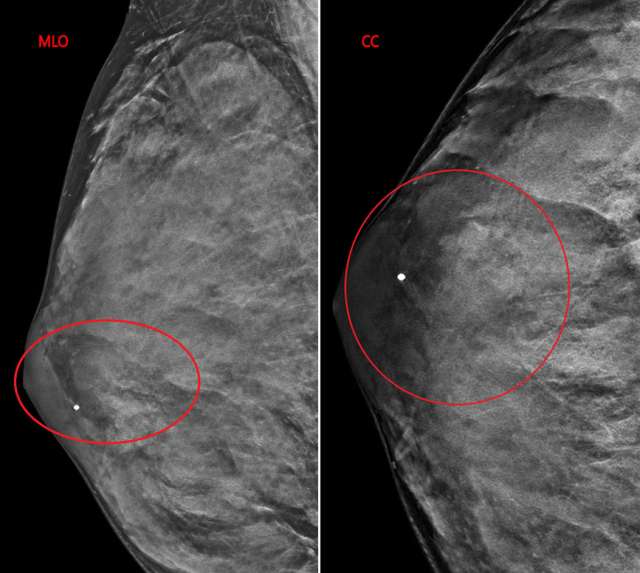

The patient underwent a diagnostic mammogram which revealed extremely dense breasts and an oval mass with circumscribed and obscured margins seen in the right breast at 9 o’clock at anterior depth (Figure 1). Targeted sonographic images were subsequently obtained which revealed a hypoechoic vascular oval mass with circumscribed margins measuring 24 x 10 x 34 mm seen in the right breast at 9 o'clock located 3 centimeters from the nipple (Figure 2). Given the patient’s medical history these findings were given BIRADS-4A and an ultrasound biopsy was recommended.